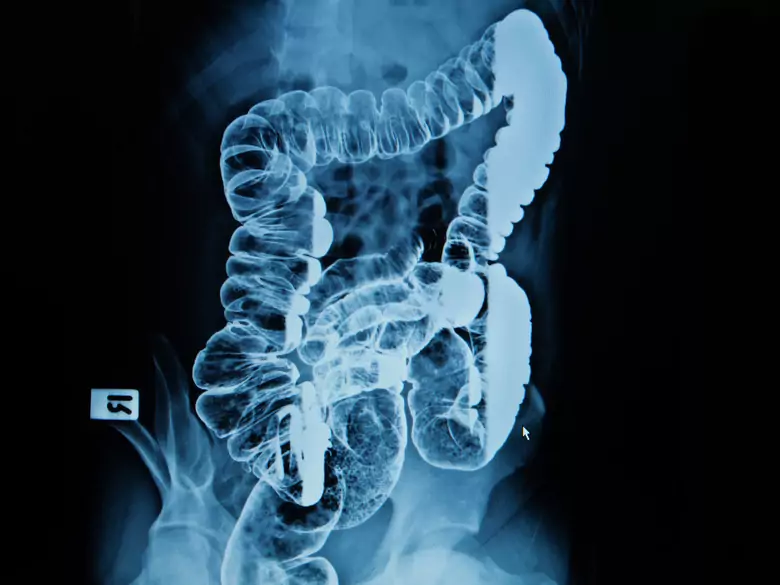

Darmuntersuchung